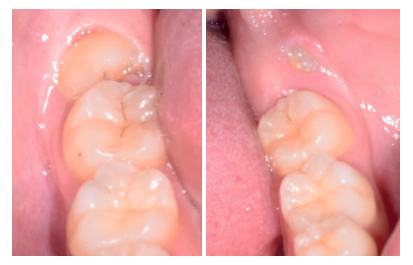

A los diez días se retiró la sutura (Figura 20), donde se puede observar una buena cicatrización de los tejidos blandos. A los 4 meses se realizó una revisión, clínica (Figura 21) y radiográfi ca, mediante radiografía panorámica (Figura 22) y un escáner de haz cónico (Figura 23), donde se puede apreciar la integración del material de injerto y una densidad ósea similar al hueso adyacente, derivando de nuevo a la paciente para comenzar el tratamiento ortodóntico.